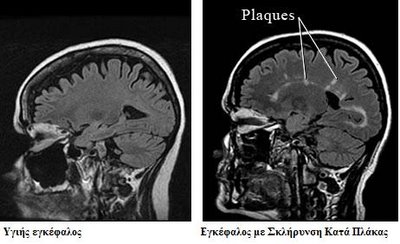

Η νέα θεραπεία φαίνεται πως μειώνει κατά 50% έως 75% τις επιθέσεις του ανοσοποιητικού συστήματος του ίδιου ασθενούς εναντίον της μυελίνης, του μονωτικού και προστατευτικού στρώματος των νεύρων του στον νωτιαίο μυελό, τον εγκέφαλο και το οπτικό νεύρο. Όταν η μυελίνη καταστραφεί, τα ηλεκτρικά σήματα δεν μπορούν να μεταδοθούν σωστά από και προς τον εγκέφαλο, με συνέπεια μια σειρά από συμπτώματα ήπια (π.χ. μούδιασμα στα άκρα) έως σοβαρά (παράλυση και τύφλωση).